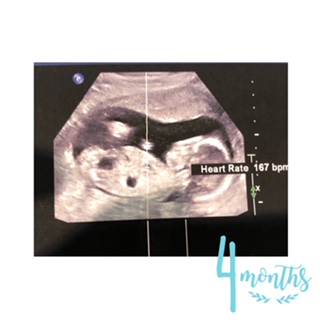

但試問邊一個準媽媽唔想準爸爸陪伴喺身邊,一齊感受同bb嘅一次,例如:第一次聽到佢嘅心跳(當時我同先生第一次聽到bb既心跳時,我地兩個都眼濕濕望住對方,個一刻真係咩都代替唔到);一齊發現bb既性別(呢個有一件趣事想同大家分享,當日我問醫生以家會唔會知bb既性別架?醫生:其實我見到架啦,我知道架啦~之後佢突然問我地,見到未呀?我地望住部電視,下?邊到呀?醫生就話:下?咁大條都睇唔到?之後我同準爸爸就一齊大笑);一齊留意bb既每一次唔同既小動作(食手手,d腳仔放到頭仔到),同埋第一次照3D見到bb既樣,大家即刻討論似邊個似邊個,呢d時刻真係好難忘。我好多謝我先生每一次產檢都陪伴係我身邊同我一齊分享bb既每一個時刻;我相信就算各位準爸爸不可以陪準媽媽去產檢都好,佢地心入面都一定會好掛住準媽媽同bb,佢地都係默默地努力工作比更好既環境比媽媽同bb。